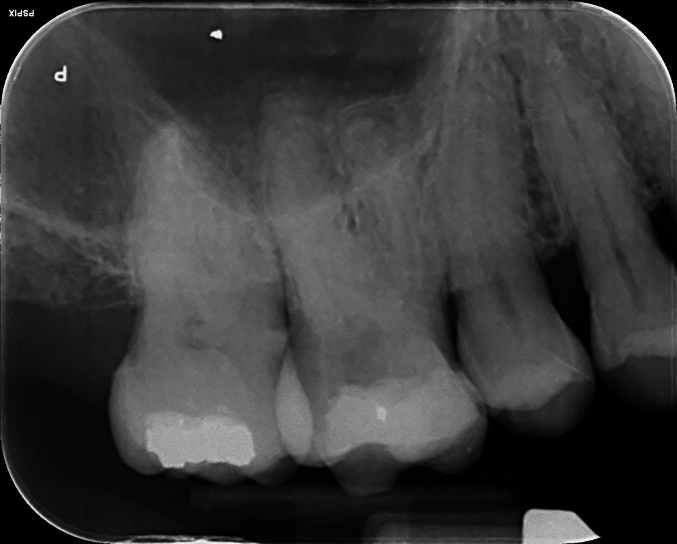

Upper Premolar and Molar root canal treatment and restoration